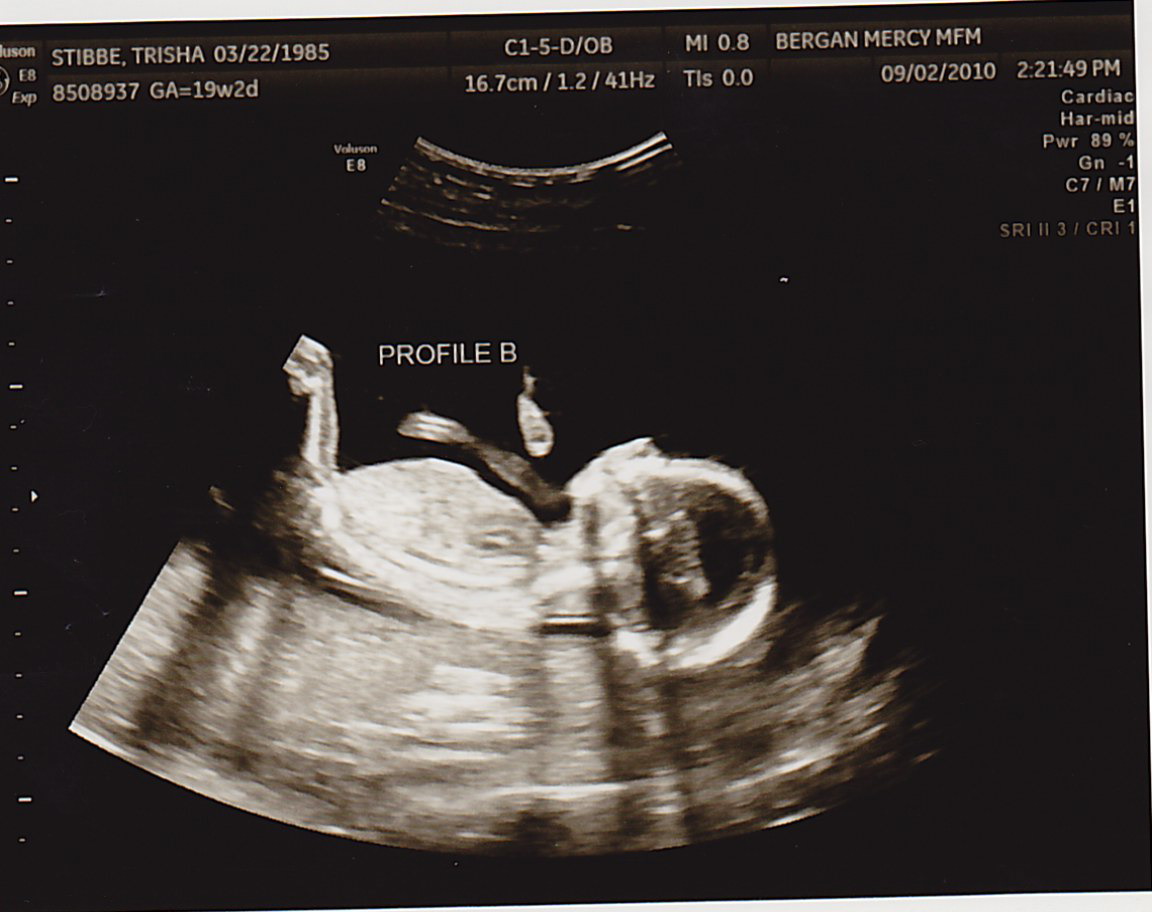

TODAY was a great appointment- we found out Baby B had a lot more fluid around himself!!! That means I didn’t have to have more fluid drained (at least for today). Baby A was 8oz and Baby B was 6oz. This is still good news, because two weeks ago Baby A was 6oz and Baby B was 4oz. As long as they’re both gaining the same amount of weight from here on out, we’re very positive everything will be okay. The difference between them just needs to continue to lessen.